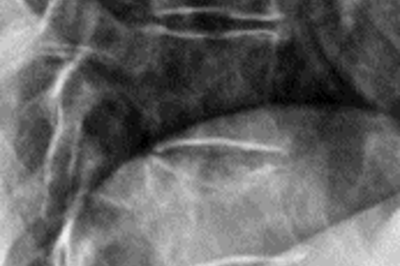

• Wirbelbruch mit Spinalkanalstenose

Röntgenbild Wirbelbruch mit Spinalkanalstenose

Traumatische, komplette Berstungsfraktur mit hochgradiger Spinalkanalstenose